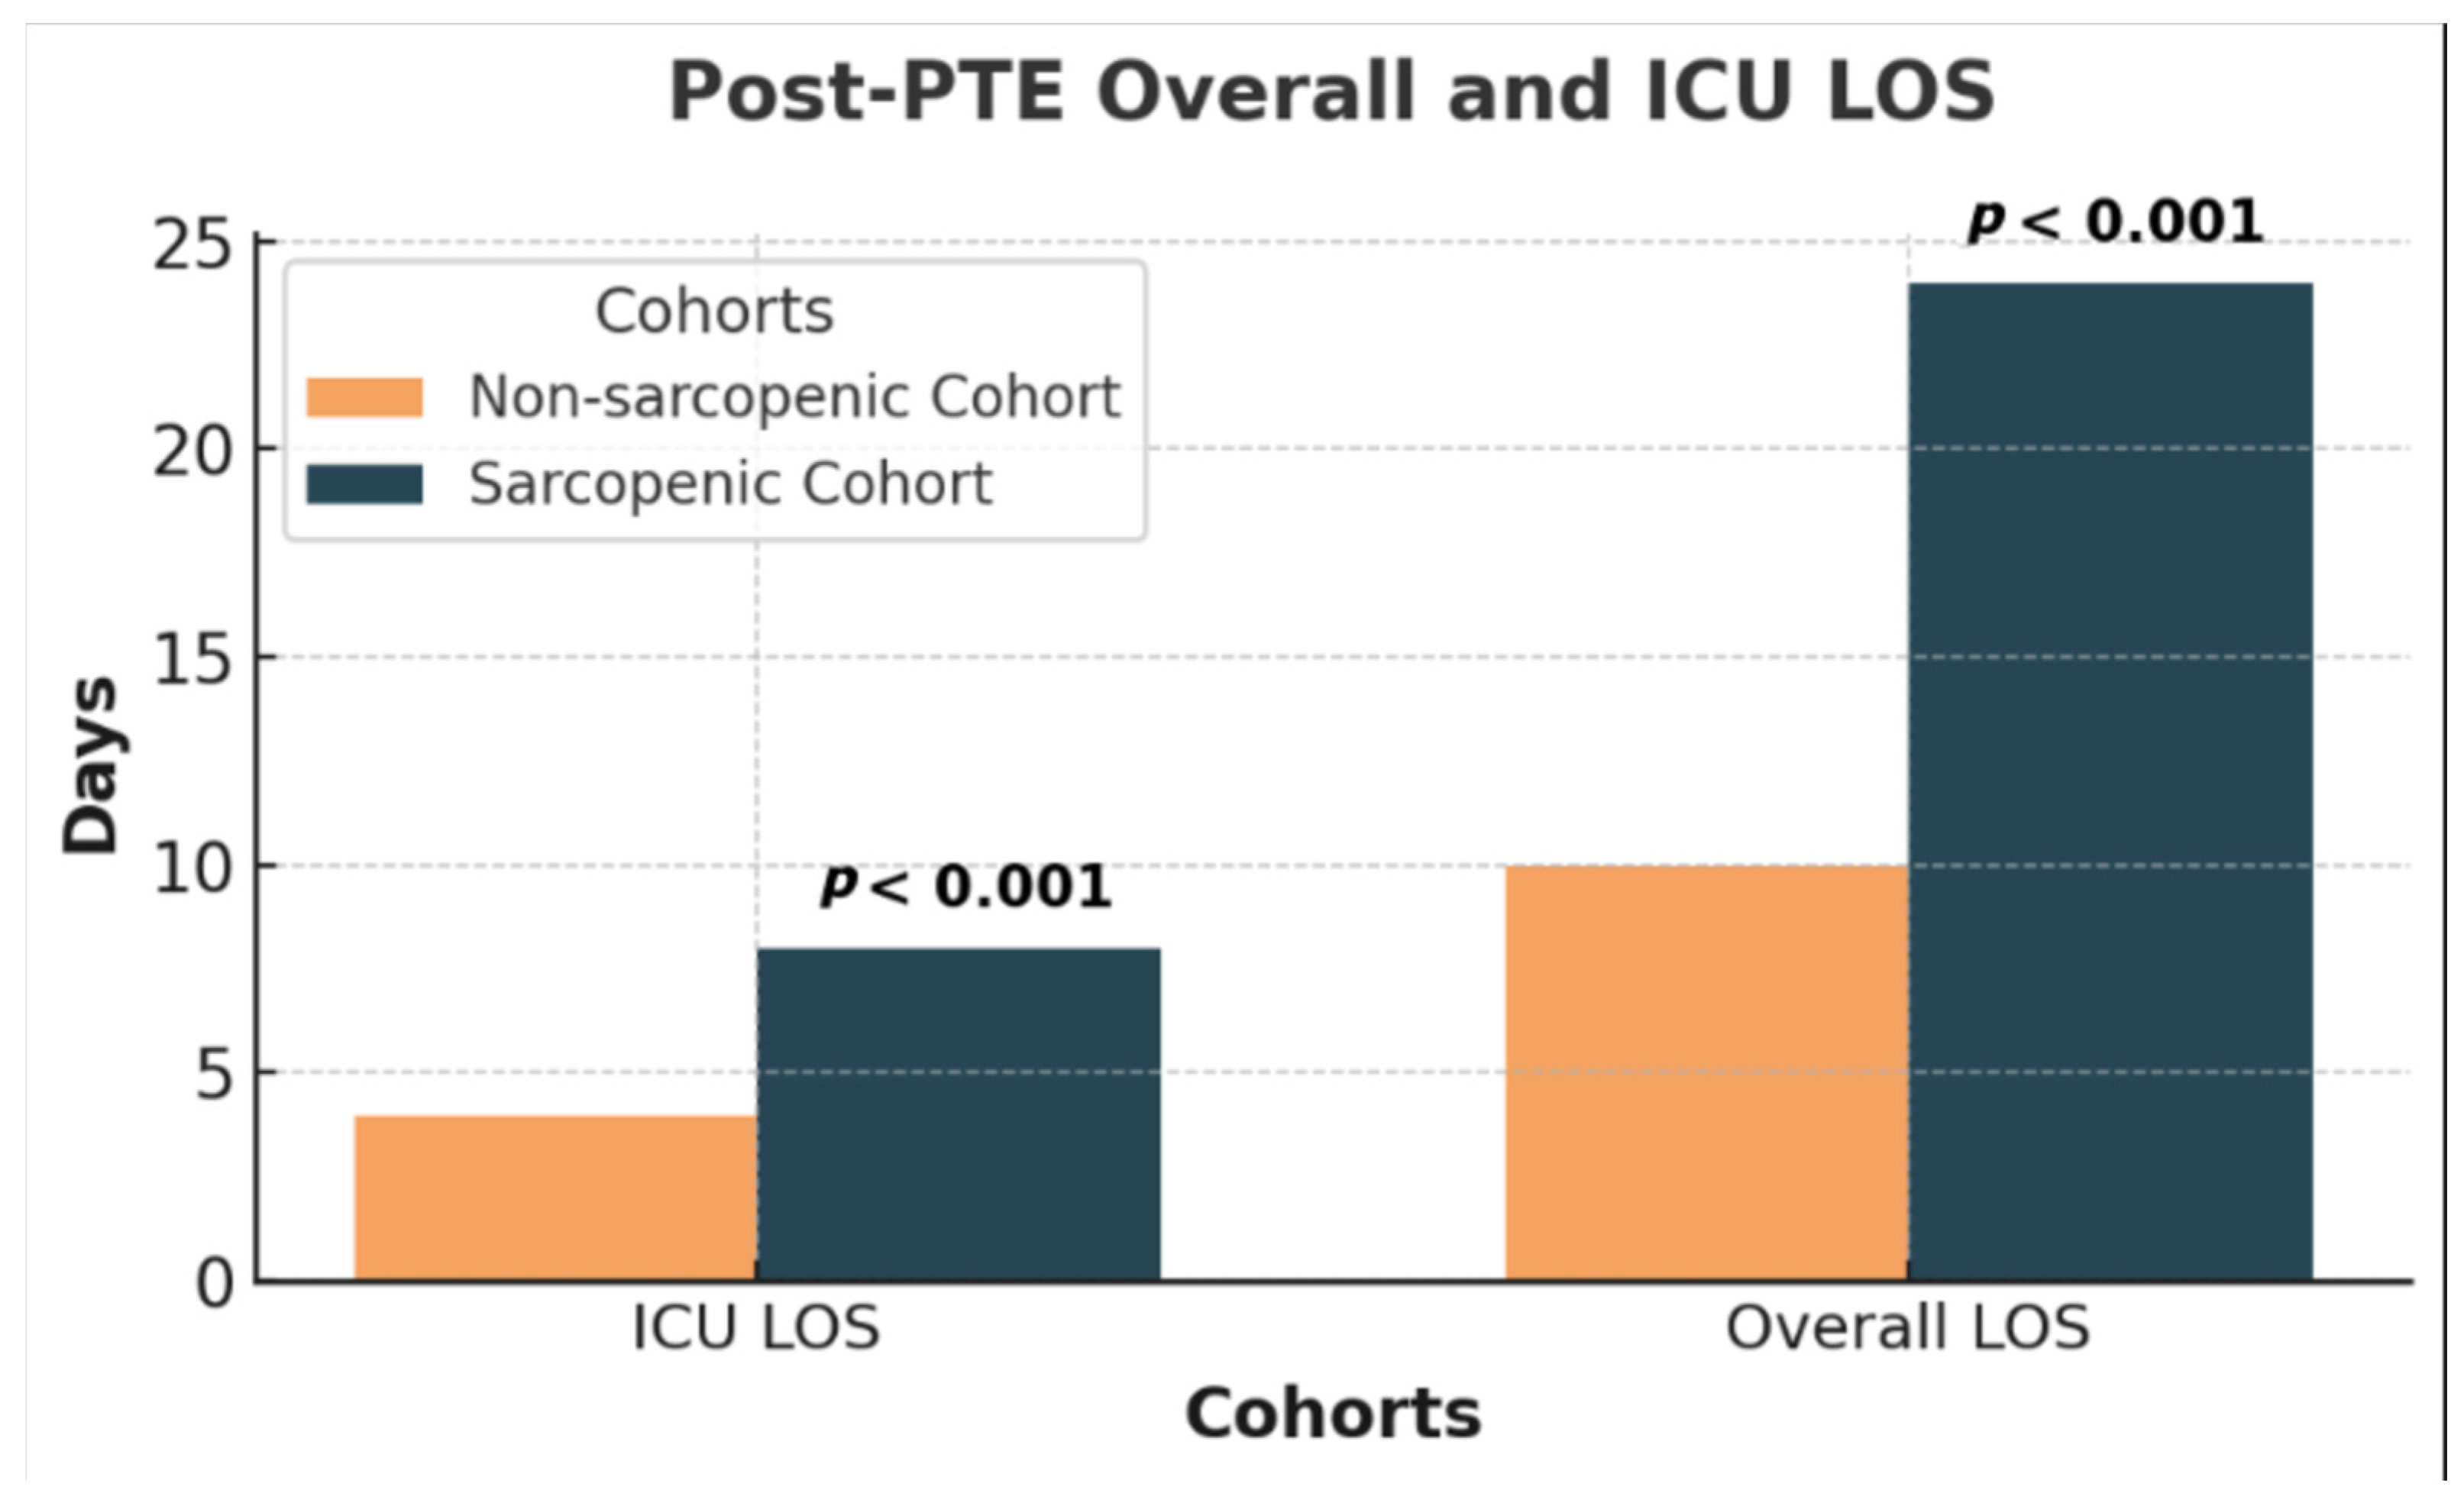

3.2. Post-Intervention

3.3. Clinical Course, Biomarkers, 6MWD, and Post-PTE Specific Outcomes

| Post-PTE ICU LOS (days) | 4 (p25 = 3, p75 = 10) | 9 (p25 = 5, p75 = 34) | 4 (p25 = 2, p75 = 7) | <0.001 |

| Post-PTE Overall LOS (days) | 14 (p25 = 7, p75 = 24) | 24 (p25 = 12, p75 = 41) | 11 (p25 = 7, p75 = 17) | <0.001 |